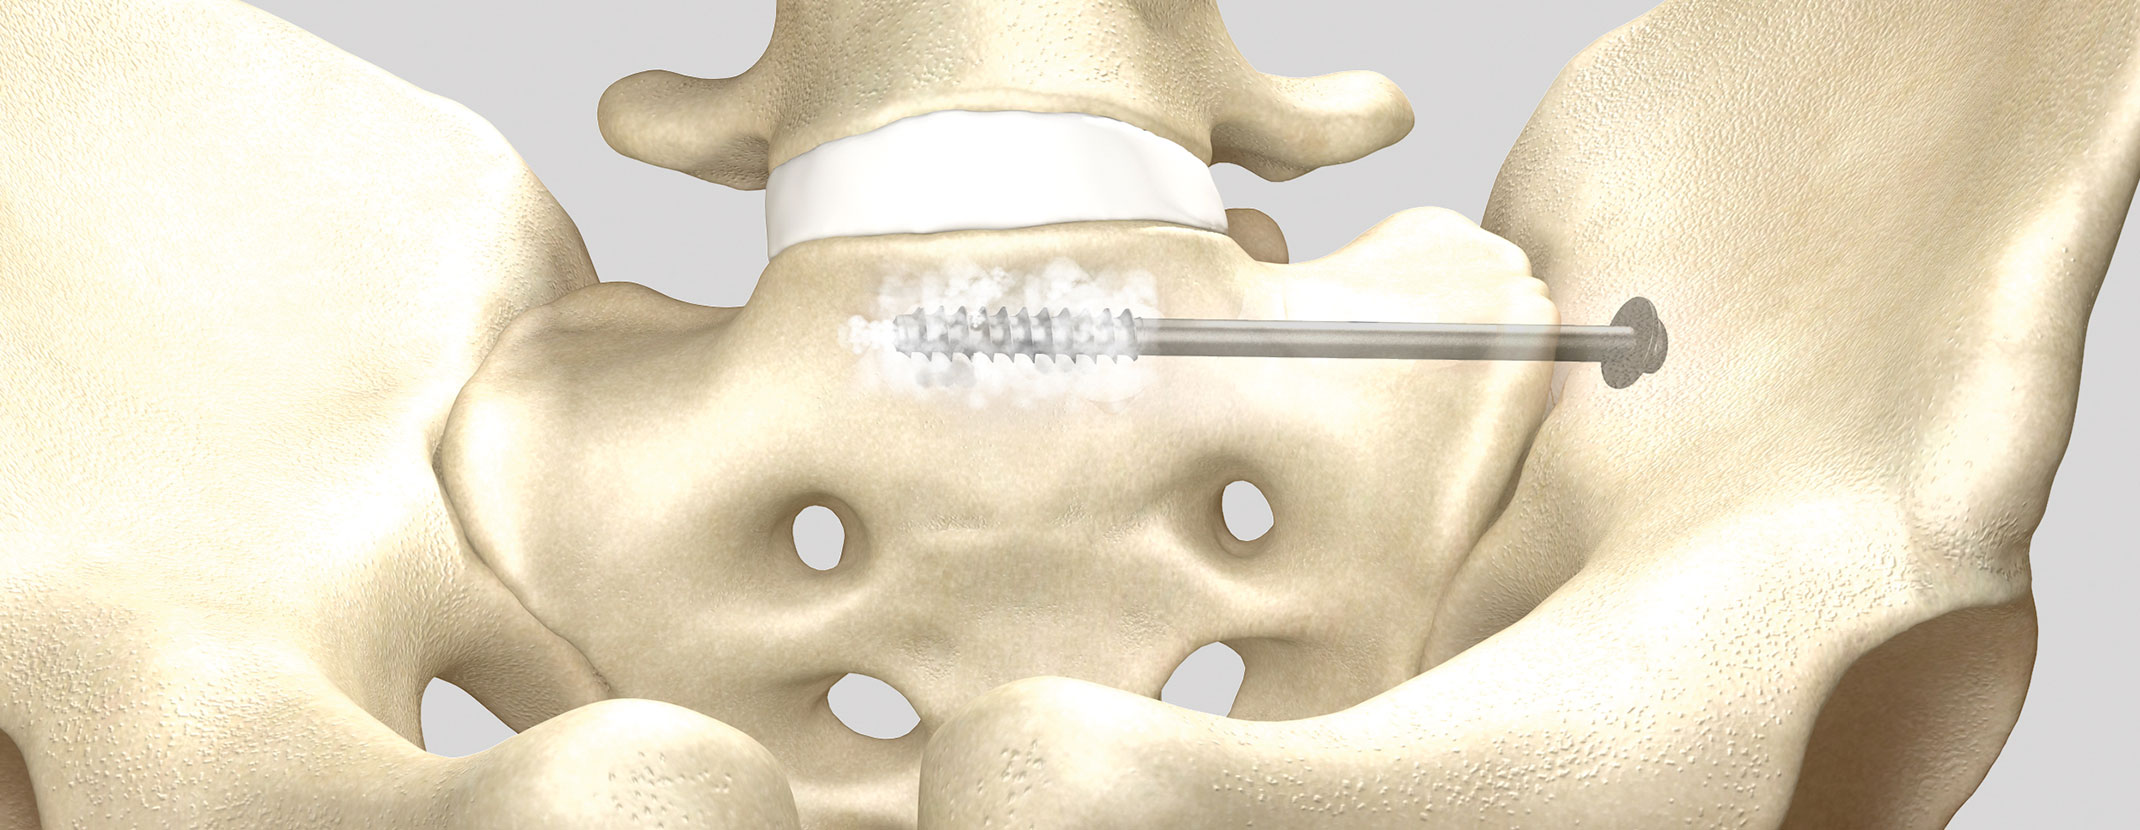

Königsee Implantate ist eines der führenden deutschen Medizintechnikunternehmen auf dem Gebiet der Osteosynthese. Seit über 30 Jahren entwickelt, produziert und vertreibt unser Unternehmen Implantate und Instrumente für die Traumatologie und Orthopädie. Die Motivation unserer täglichen Arbeit zielt auf die Entwicklung und Optimierung gesundheitsfördernder Produkte ab – immer mit dem Augenmerk auf dem Wohl des Patienten. Mit unseren innovativen Produkten für nahezu alle Knochenabschnitte – vom Schlüsselbein bis zu den Zehen – verkürzen wir aktiv den Heilungsprozess von Frakturen gegenüber konventionellen Behandlungsmethoden, was im Idealfall sowohl die Kosten für die Klinik als auch die Belastung für den Patienten senkt.

Innovative Implantate

Gemeinsam mit unseren Anwendern entwickeln wir Produkte, die speziell abgestimmt auf die heutigen Anforderungen der modernen Medizintechnik sind. Dabei überzeugt vorallem die gelieferte Qualität der klimaneutral produzierten Implantate. Alle Implantate sind auch steril verpackt erhältlich.